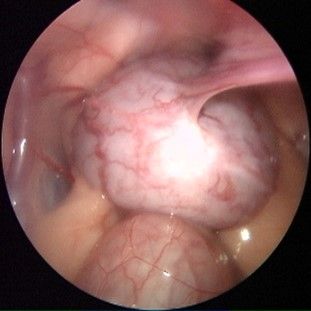

Endoskopische Kastration

Eine schonende Methode zur Entfernung der Eierstöcke oder der gesamten Gebärmutter.